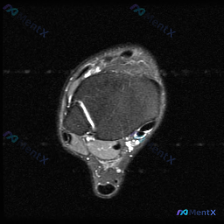

看到这个踝关节MRI的病例,整理了完整的影像资料和分析思路,和大家分享讨论。 病例影像基础信息 这是踝关节MRI T2加权轴位图像,扫描层面为踝关节远端,可见距骨体及周围软组织结构,图像对比度满足观察要求,T2加权像液体呈高信号。 核心影像发现 1. 骨结构:距骨及周围骨性结构骨髓无异常高信号,骨皮...

看到这份踝关节MRI读片资料,整理出来和大家分享讨论,病例本身很有代表性,容易踩坑。 病例影像基本信息 这是放射影像-脚踝MRI-T2序列轴位片,我们先把读到的信息整理清楚: 1. 骨性结构:距骨体部骨皮质完整,骨髓信号正常,没有骨髓水肿、骨折或骨皮质中断;关节间隙清晰,关节面平整 2. 肌腱韧带:...